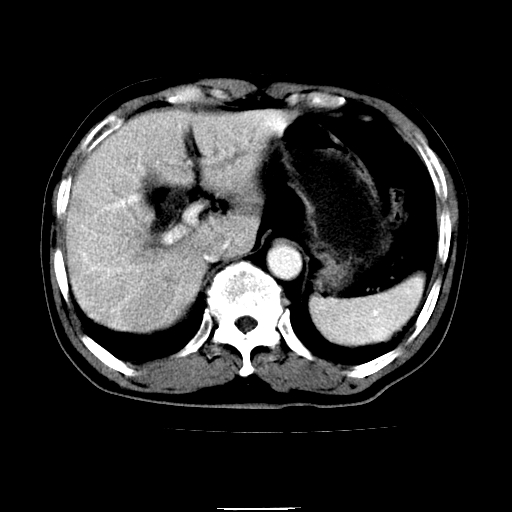

以下是引用chenqiong在2010-3-25 20:56:00的发言:[br]1、胆囊炎,胆囊息肉[br]2、肝内胆管及胆总管扩张,胆总管下端结石[br]3、十二指肠乳头旁憩室

以下是引用zxl51642在2010-3-26 10:47:00的发言:[br]胆囊炎,胆囊息肉,胆总管扩张,但未看到明显肿块,肝内胆管扩张不像恶性,炎性狭窄或阴性结石可能吧,建议mrcp,右肾小囊肿